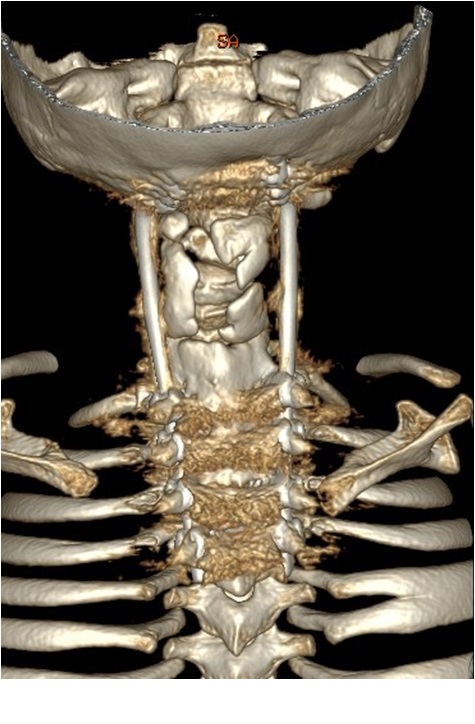

- Figura 12. Tomografía reconstrucción 3 D. 2 años postoperatorio